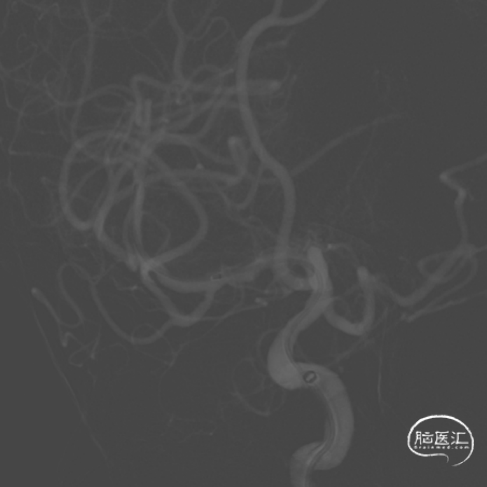

脑血管造影:右侧大脑中动脉M1段局部瘤样突起,远端重度狭窄,考虑右侧大脑中动脉M1段夹层动脉瘤。

右侧颈内动脉正侧位和右侧大脑中动脉工作位造影。

治疗之前3D和工作位(测量病变处近远端血管管径,M1近端1.9mm,M1远端1.7mm)。